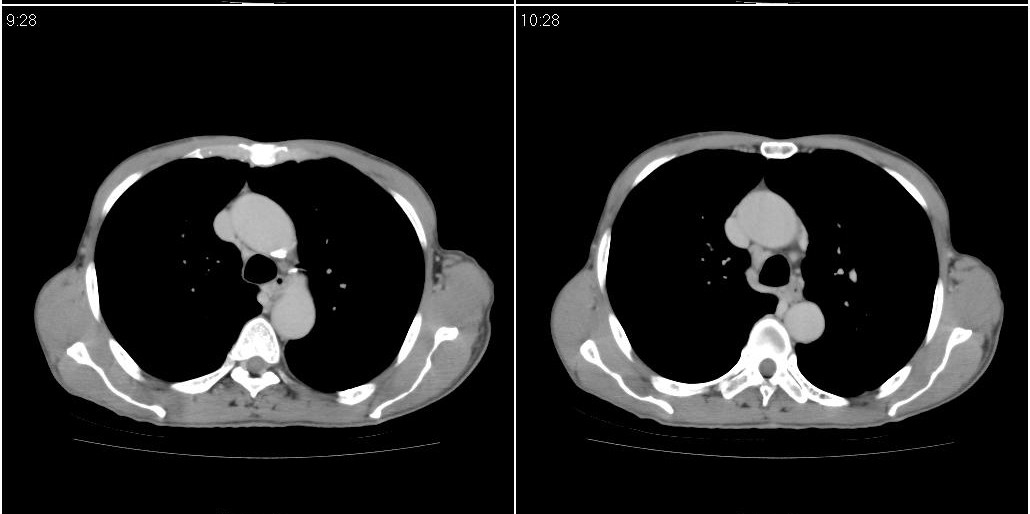

标题: ct增强:

右肺中叶阻塞性不张及肺炎,高度怀疑支气管占位,建议纤支镜检查!

考虑右肺中叶感染。左肺下叶支扩。

右中肺阻塞性炎症,建议纤支镜!双下支扩感染。

1)右肺中叶慢性炎症并支气管扩张,节段性肺不张。2)两肺下叶支气管扩张。